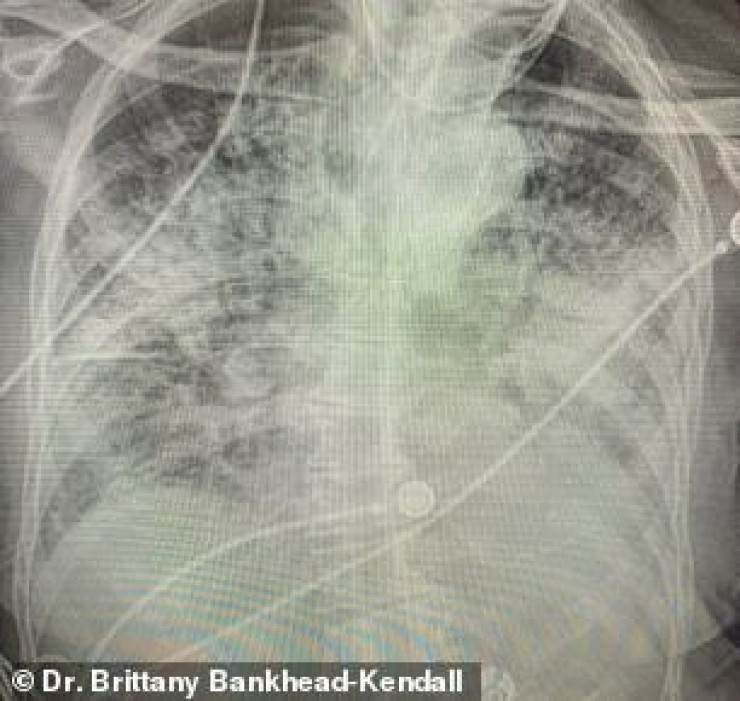

Доцент Центра медицинских наук Техасского технологического университета, доктор Бриттани Бэнкхед-Кендалл показала три рентгеновских снимка легких: здорового человека, курильщика и пациента с коронавирусом.

По словам хирурга, легкие выздоровевших пациентов с COVID-19 выглядят намного хуже, чем у курильщиков. Снимок выглядел почти полностью белым. Врач пояснила, что помутнение легких обычно указывает на то, что они наполнены такими веществами, как жидкость или бактерии, а также плотными рубцами и повреждениями.

"Легкие после коронавируса выглядят хуже, чем любые ужасные легкие курильщика, которые мы когда-либо видели. И они разрушаются", - заявила она.